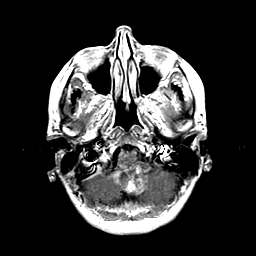

Metastatic Adenocarcinoma of the Colon: T1-weighted MR -- Slice #4

[Home][Help][Clinical] Slice 4